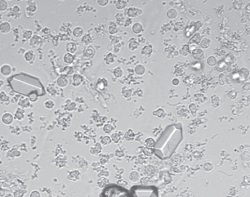

Микроскопические изображения осадка мочи в полном поле зрения

Автоматическое распознавание частиц мочи при помощи автоматического модуля анализа изображения (AIEM)

| Измеряемые параметры | RBC, WBC, WBCc, HYA, PAT, EPI, NEC, BAC, YEA, CRY (CaOxm, CaOxd, URI, TRI), MUC, SPRM |